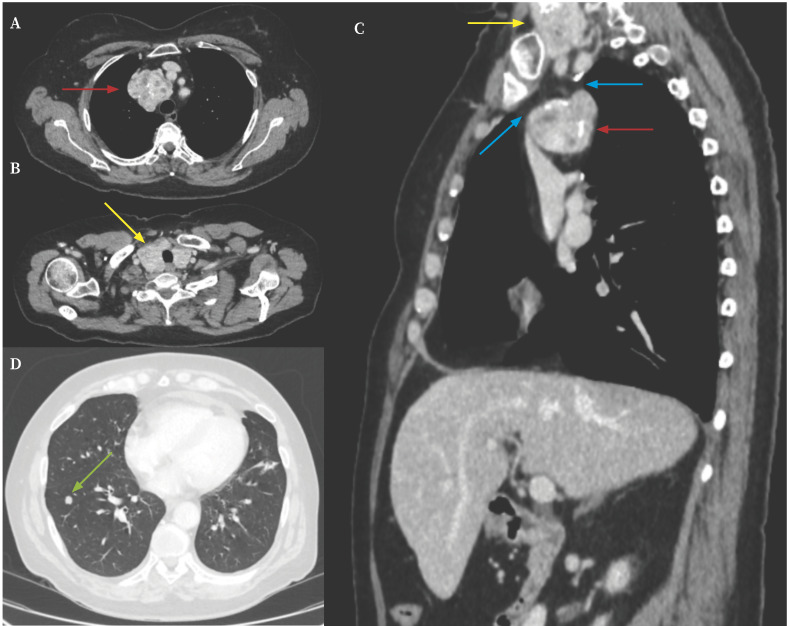

Intrathoracic goiters can be classified as primary or secondary. Primary intrathoracic goiters are characterized by the absence of any anatomical connection with the cervical thyroid gland, in contrast to secondary intrathoracic goiters. A rare variant, termed mixed or combined intrathoracic goiter, involves the synchronous presence of both primary and secondary components within the thoracic cavity. Given the rarity and the diagnostic challenges associated with these conditions, we report the case of a patient who presented with a multinodular goiter and a separate right paratracheal mediastinal mass. The latter was identified as ectopic thyroid tissue, consistent with a primary intrathoracic goiter. We describe the diagnostic approach used to differentiate the mediastinal mass from other thoracic pathologies, as well as the successful surgical management performed via a minimally invasive technique and facilitated a rapid and uneventful postoperative recovery.